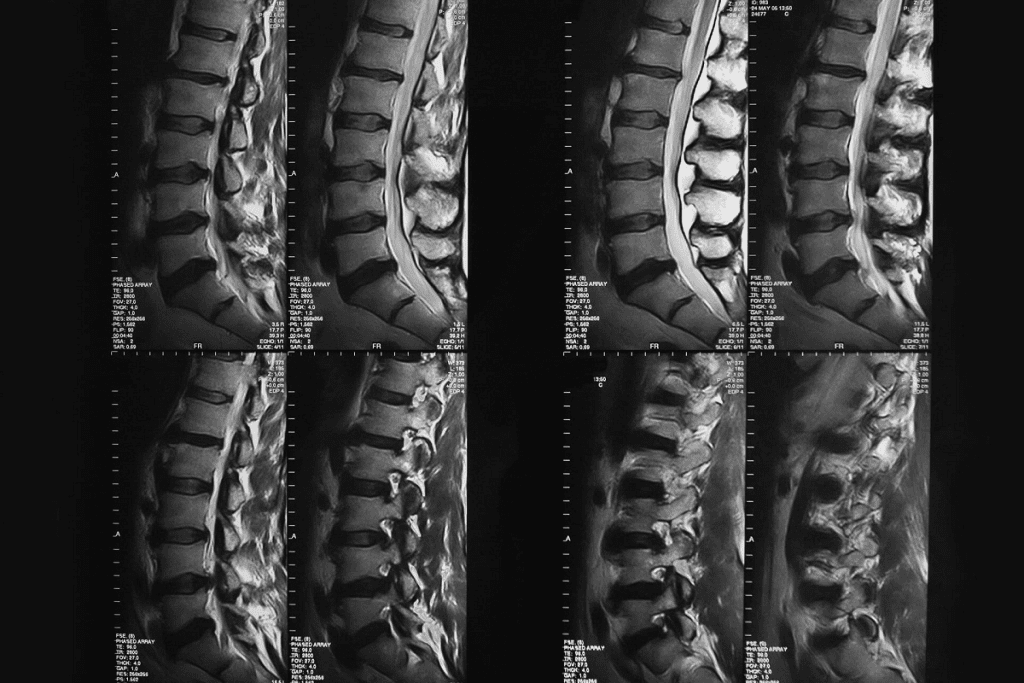

Metabolic Bone Diseases: Insights from Bone Scans

Bone scans give us a special look at metabolic bone diseases. They help us understand conditions like Paget’s disease and osteomalacia. These diseases mess with bone metabolism, causing changes that bone scans can spot.

Metabolic bone diseases include many disorders that harm bone health. Paget’s disease and osteomalacia are two examples. If not treated well, they can really hurt a patient’s life quality.

Paget’s Disease and Osteomalacia Patterns

Paget’s disease makes bones break down and rebuild too much. This can cause deformities and serious problems. Bone scans show the special patterns of Paget’s disease, highlighting areas where bone activity is high.

Osteomalacia softens bones because of vitamin D problems. Bone scans can find where bones are less dense and less active.

| Condition | Bone Scan Findings | Clinical Implications |

| Paget’s Disease | Increased bone activity, characteristic “hot spots” | Potential for deformities, fractures, and neurological complications |

| Osteomalacia | Decreased bone density, “cold spots” | Increased risk of fractures, bone pain, and muscle weakness |

Monitoring Treatment Response in Metabolic Conditions

Bone scans are great for diagnosing and tracking metabolic bone diseases. They help doctors see how treatment is working. This way, they can change plans to better manage the disease.

For example, in Paget’s disease, bone scans show if bisphosphonate therapy is working. They look for less bone activity. In osteomalacia, scans track how vitamin D helps improve bone density and activity.

Thanks to bone scans, doctors can give patients more tailored and effective care. This is a big step forward in treating metabolic bone diseases.